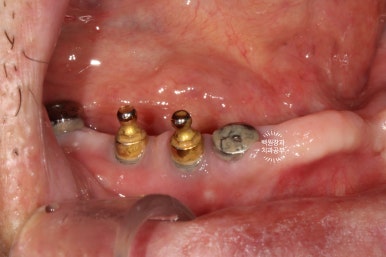

이제 치유기간이 지났으니, 뿌리 속 임플란트에 기둥을 연결하고 치아머리를 붙여드릴 시간인데요,

사실, 너무너무 오랜만에 틀니 대신 치아를 갖게 되시는 상황이라 '재활치료'의 개념을 갖는 시간이 필요합니다.

보시면 치아와 기둥이 모두 연결되있는 것을 확인하실 수 있죠? 그리고 잘~보시면 임시치아의 외형도 보입니다.

그래서 사용하시는 것이 바로 이 임시치아입니다.

당연히 치아처럼 생겼지만, 사실 재료는 단단한 플라스틱 정도로 생각하시면 되는 레진치아입니다.

이 임시치아는 높이 조정이 쉽기 때문에, 이 임시 보철물을 사용하시면서 잃어버렸던 아래턱의 자리를 찾아간다고 생각하시면 됩니다.

이제부터는 임시틀니가 필요없어지기 때문에, 환자분의 삶의 퀄리티가 급격히 올라갑니다.

씹는면에서 본 임시치아입니다.